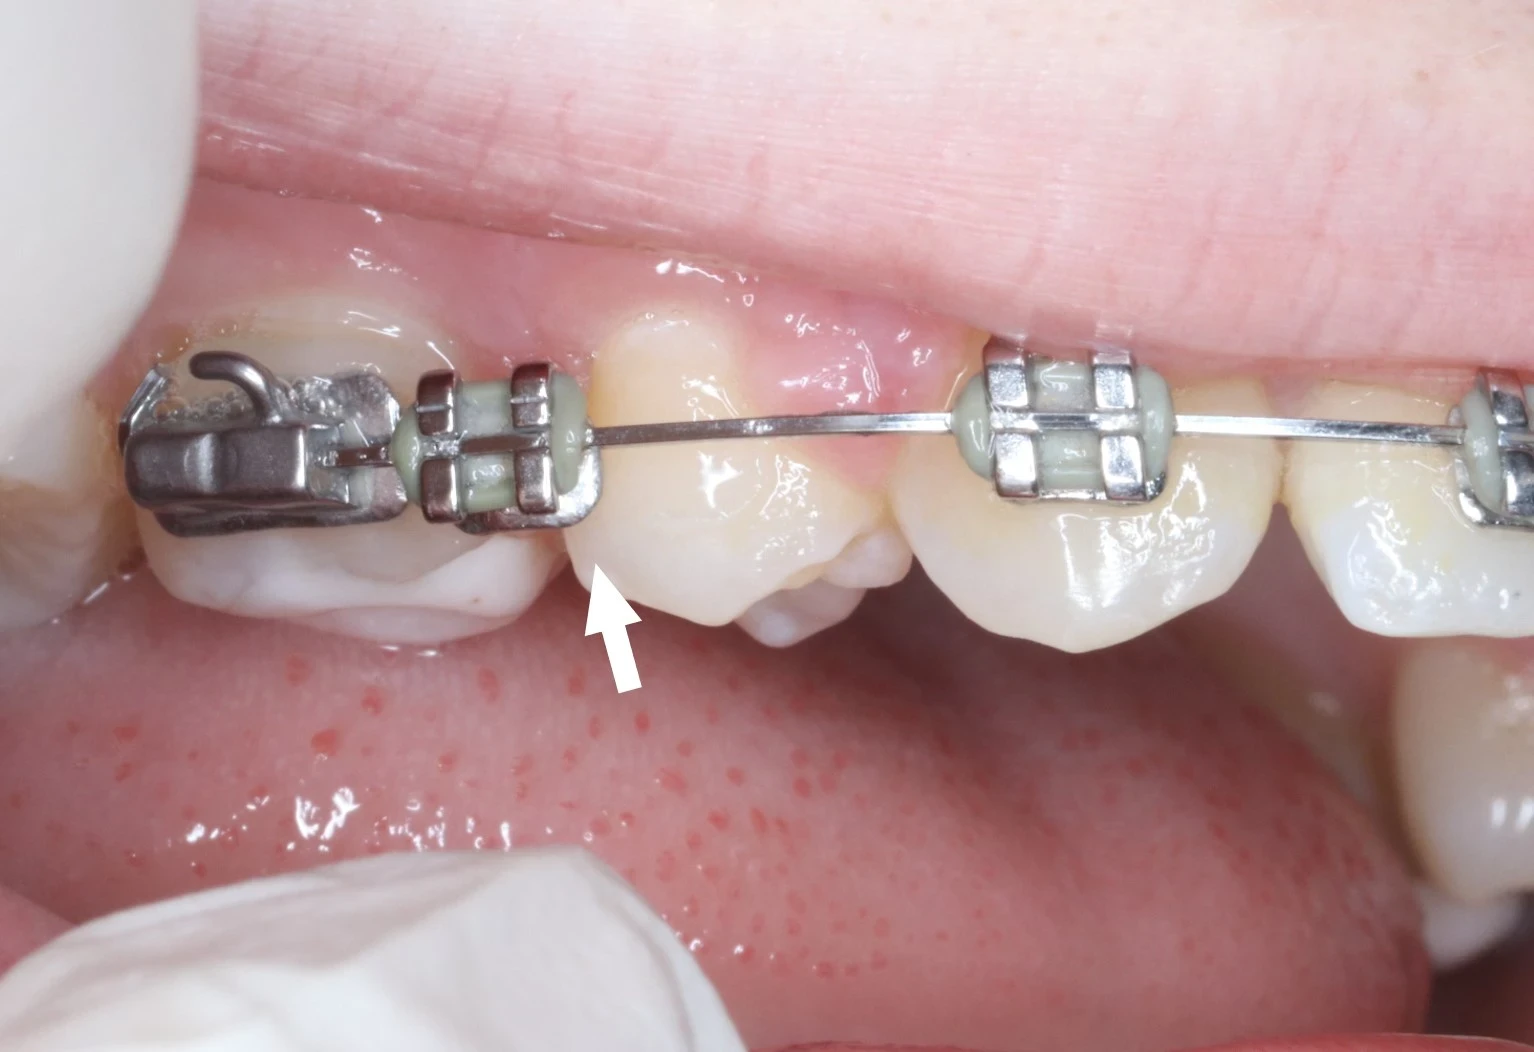

Les appareils multi-attaches traditionnels

Principalement utilisée chez les enfants et les adolescents, cette technique nécessite la pose de brackets (attaches) sur la face externe (et donc visible) des dents (en vestibulaire). Collées, ces attaches seront en métal ou en céramique, afin d’atténuer le caractère visible du traitement.

À savoir :

À la fin de chaque traitement, le Dr C. MAYODE prévoit une contention, incluse dans le traitement, afin de garantir la stabilité de ce dernier dans le temps.